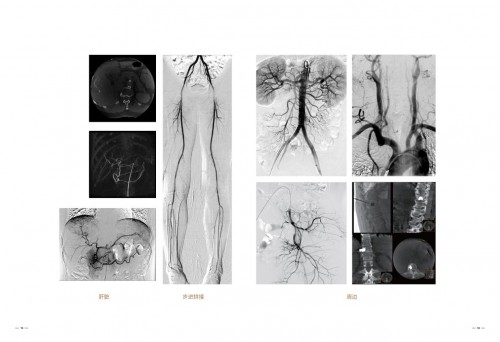

万东不仅在国内销量持续增长,自主研发的高端产品也走出国门,赢得国外客户青睐 。 2019年,新一代的万东金刚DSA(减影血管造影设备)也成功出口多米尼加共和国。 在多米尼加国家血管医院,万东金刚DSA入驻仅仅三个多星期就帮助当地医疗专家成功完成了二十几台心脏手术。对于金刚DSA,当地专家认为:“操作便捷方便、图像细节丰富,令人折服。”

万东DSA先后与宣武医院、阜外医院、同仁医院、山东影像所、武汉中心医院等,建立临床验证合作,累计用户400多家,实施临床手术200多万次,产品性能通过临床检验不断提升。 03金刚巨人,超乎所见 2019年,万东推DSA 家族的集大成者—— “金刚” DSA。金刚融入了国际先进的软件和硬件技术,产品运行更加稳定,图像更加清晰。

金刚DSA“八”轴运动结构,L臂、C臂、床台和谐动力配合,快速灵活实现术中各种摆位移动。智能全轴等中心,无论机架如何变化,图像视野中心始终保持不变,方便快速智能锁定病灶。 三段式移动床台方便使用 ,120CM大进深床面板,满足机架正位股动脉穿刺需求,230CM纵向移动范围,无需移动病人即可完成全身介入手术,80CM可移动地轨床,可迅速将C臂与床体分离,快速实现CPR位,方便抢救。 介入手术的剂量高低很关键,关系到医生和患者的安全。金刚DSA在每一环节减低剂量,采用40*30微剂量平板探测器,运用智能AI 算法和AICS低剂量统筹平台,兼顾精准与低剂量,使得医生和病人在手术过程中不用为辐射问题发愁。多种智能防碰撞技术,让设备在高速复合运动中,始终照顾周全。